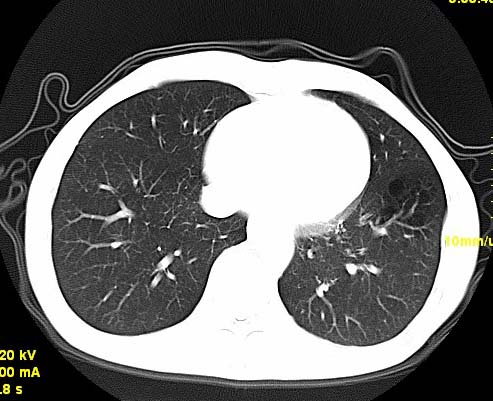

以下是引用wangzhengyuan在2007-11-11 23:31:00的发言:[br]钙化灶,看上去不像转移。

以下是引用zjzjr在2007-11-12 8:35:00的发言:[br]考虑错构瘤,建议定期复查.

以下是引用卜一在2007-11-12 5:59:00的发言:[br]病灶本身不像转移,不知有没有以前的胸部ct片,若有,则可以对比以下,若是新出现病灶,应高度警惕“转移”的可能![br]